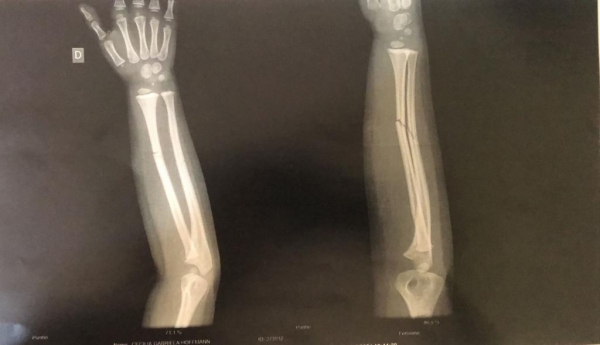

O resultado do exame (imagem acima) apresentou duas fraturas fechadas no braço da criança, que voltou para o hospital Bom Pastor após fazer o Raio-X, e ficou aguardando em um leito a transferência para algum hospital da região a fim de receber atendimento especializado.

A reportagem do Portal está acompanhando o caso da criança de 3 anos, moradora de Nova Santa Rosa, que teve duas fraturas fechadas no braço direito após cair enquanto brincava em uma cama elástica na manhã de quinta-feira (19).

A criança foi levada ao Hospital Bom Pastor no início da tarde de ontem e, por volta das 16h00, foi encaminhada à Palotina para fazer Raio-X no Hospital da Unimed, onde o município tem convênio por não estar realizando o exame - a sala está há tempo fechada e até hoje não foi colocada em funcionamento pela prefeitura.